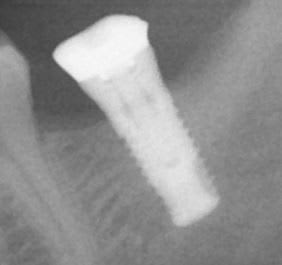

J'ai un soucis sur un vieil implant SERF 5*10, très bien ostéo-intégré mais qui manque cruellement de hauteur pour faire une couronne correcte (sur la radio est présente la "couronne" actuelle)

Peut-on démonter l'anneau esthétique pour gagner un peu de hauteur, et comment ?

Et quelle hauteur je peux espérer en gain